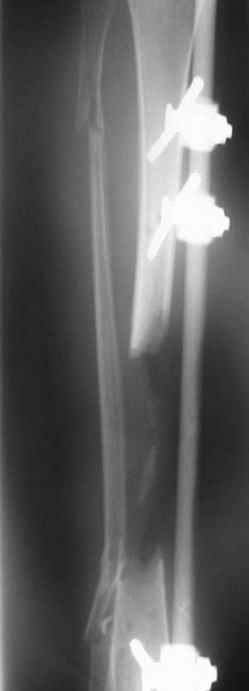

This Patient have to be treated by using Ilizarov bifocal bone transport, aproximatly as showen here.

Your Dr. Castro